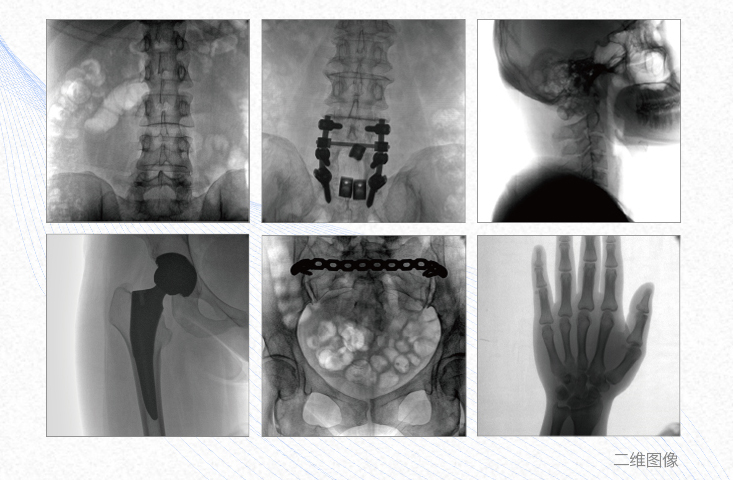

1、脊柱外科

有效重建復雜的脊柱三維模型,提供準確的二維、三維圖像,提高螺釘植入的準確性,縮短手術(shù)時間,減少并發(fā)癥的概率,降低輻射的攝入。

2、創(chuàng)傷外科

例如骨盆骨折內(nèi)固定術(shù),可術(shù)中三維重建髖臼關節(jié)面,準確定位并植入螺釘,有效縮短螺釘植入的時間和透視暴露時間,減少術(shù)中及術(shù)后并發(fā)癥發(fā)生的概率。

3、關節(jié)外科

主要應用于肩關節(jié)、肘關節(jié)、髖關節(jié)、膝關節(jié)的關節(jié)置換及解剖復位的定位。它可以準確地置入假體,減少輻射時間,降低輻射劑量。

4、截骨矯形外科

例如治療先天性脊柱側(cè)后凸畸形,可有效引導術(shù)者植入后路螺釘并切除半錐體,達到滿意的截骨矯正效果。